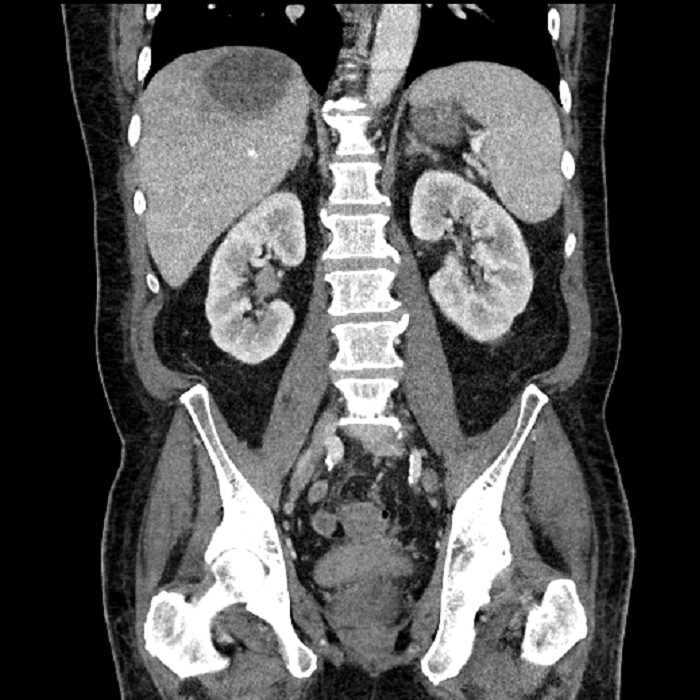

Age: 63

Sex: Male

Indication: Abdominal pain

• Large fluid density structure in hepatic segments 7 and 8 measuring 10 x 7 x 7 cm with internal septation and circumferential ill-defined low density compatible with edema

• Peripherally enhancing subcapsular collections along the anterior margin of the left hepatic lobe measuring 3 x 1 cm and 2 x 1 cm

• Clearly marginated fluid density structure in segment 7 and several other scattered tiny hypodensities, which likely represent cysts

• Hepatic abscess

Acute sigmoid diverticulitis complicated by a small contained perforation and a large abscess in the right hepatic lobe. Additional small subcapsular abscesses along the anterior margin of the left hepatic lobe.

• The classic CT imaging appearance is a double target sign with internal low density surrounded by an internal enhancing rim (capsule) and a low density external rim (edema)

Hepatic abscess showing the double target sign with low density internally surrounded by a thin inner enhancing rim (red arrow) and ill-defined outer low density rim (yellow arrow). Blue arrow indicates an internal septation. Red arrows: additional smaller subcapsular abscesses. Red arrow: focal contained perforation associated with diverticulitis.